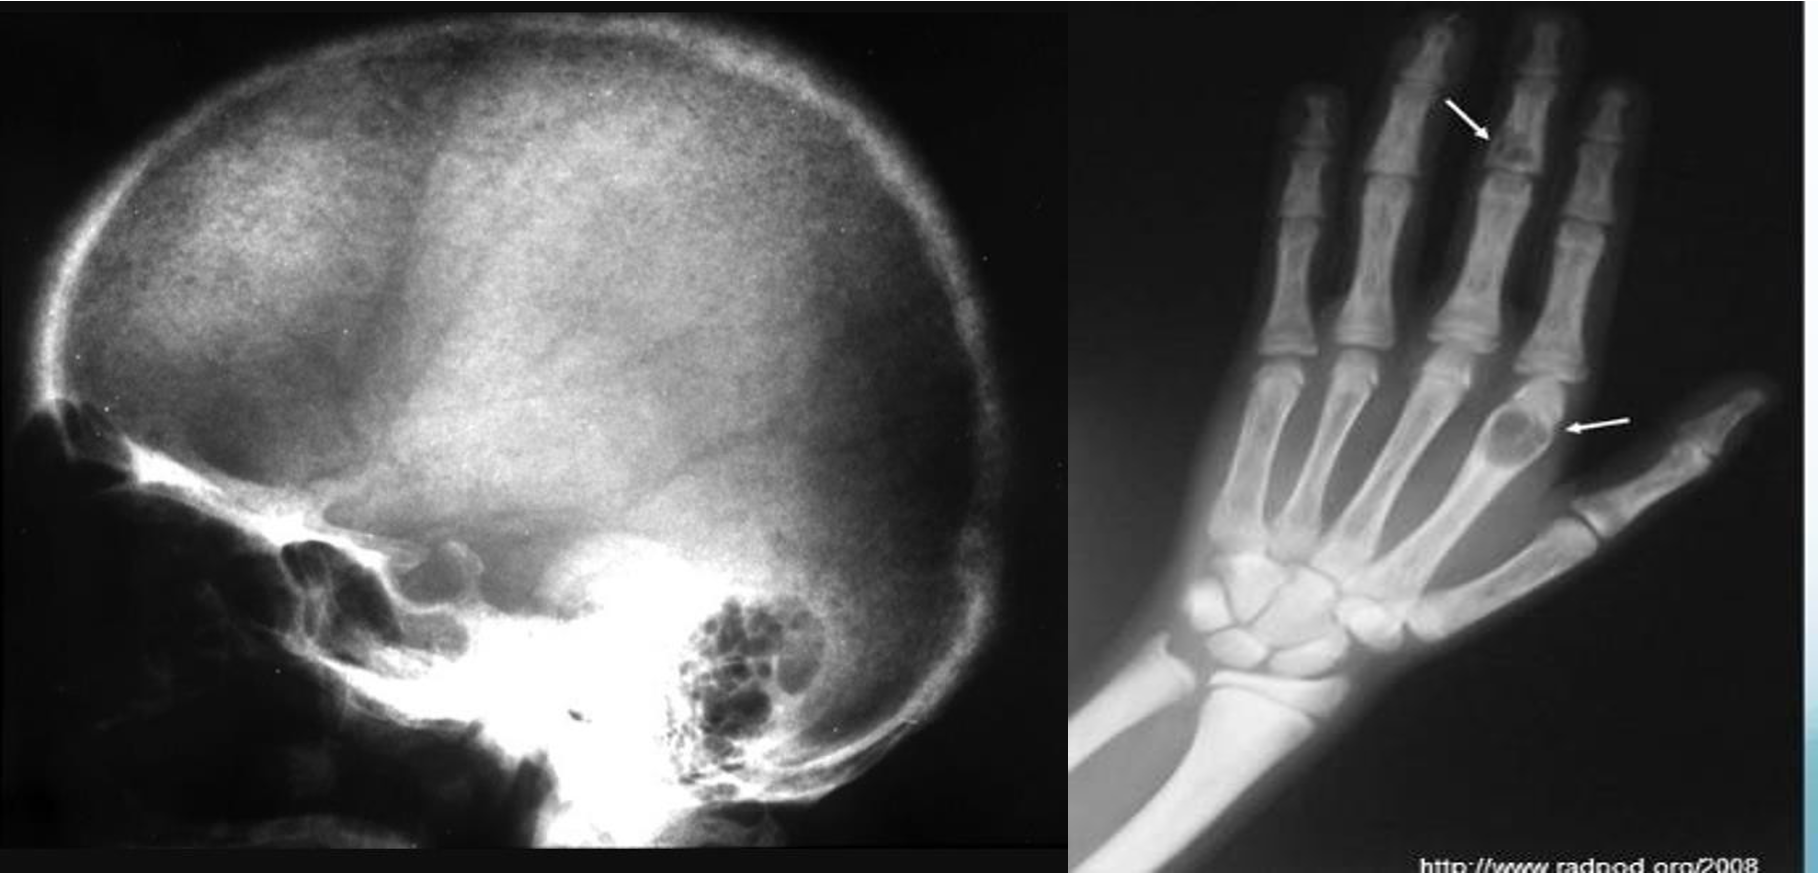

Brain Imaging

Epidural

- ipsilateral pupil diltation

Treatment: ligation of artery

Subdural

Bridging vein from brain to dural space - commonly elderly/pediatrics

- Epidural - shifted lenticular

- Subdural - crescent

- Subdural -

- Epidural